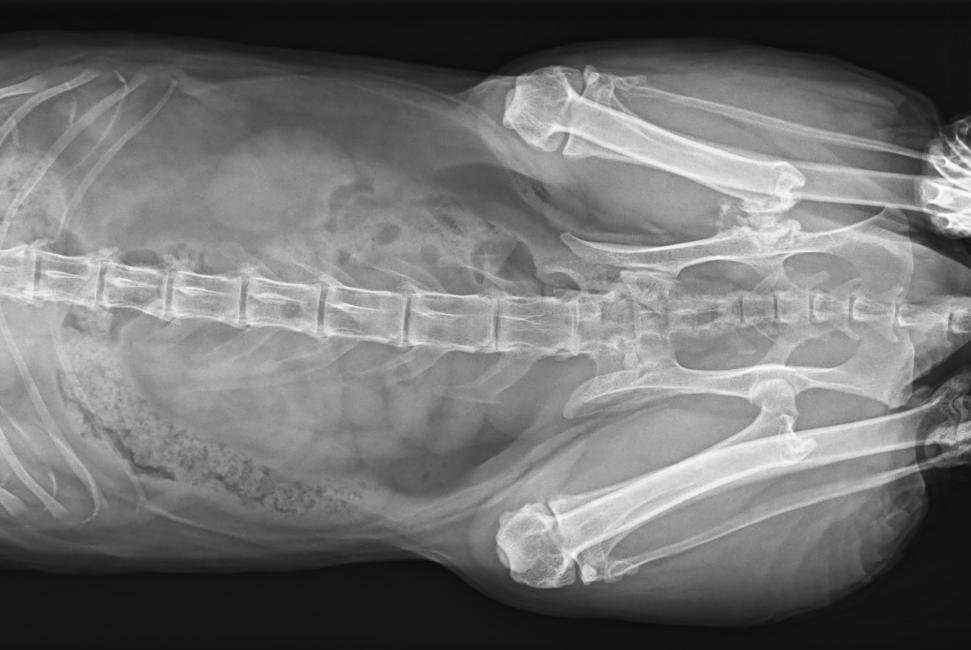

專為拍攝寵物設(shè)計 VET1900 寵物DR

● 可浮動床面設(shè)計,滿足大部分中小型寵物檢查

● 靈巧機(jī)架設(shè)計,近臺操作,手動/遙控曝光,結(jié)構(gòu)靈活緊湊

● 占地面積小,滿足多種安裝條件